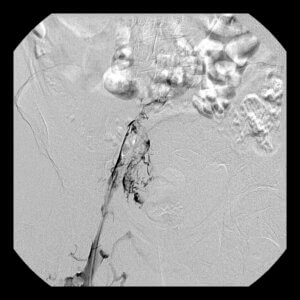

If a patient cannot be treated with blood thinners (due to an increased risk of bleeding) and is not felt to be a candidate for catheter-directed thrombolysis, then placement of an Inferior Vena Cava Filter may be indicated. Filters can also be placed in patients who are felt to be at significantly increased risk for DVT formation who would be unable to tolerate a pulmonary embolism. A filter is a small device that is placed directly into the Inferior Vena Cava, which is the main vein draining blood from both legs. The filter stays within this vein and traps any clot that travels from the legs before it is able to reach the lungs. Filters can be a permanent device, but often they are removed when they are no longer needed. This procedure is done on an outpatient basis at one of our local hospitals.